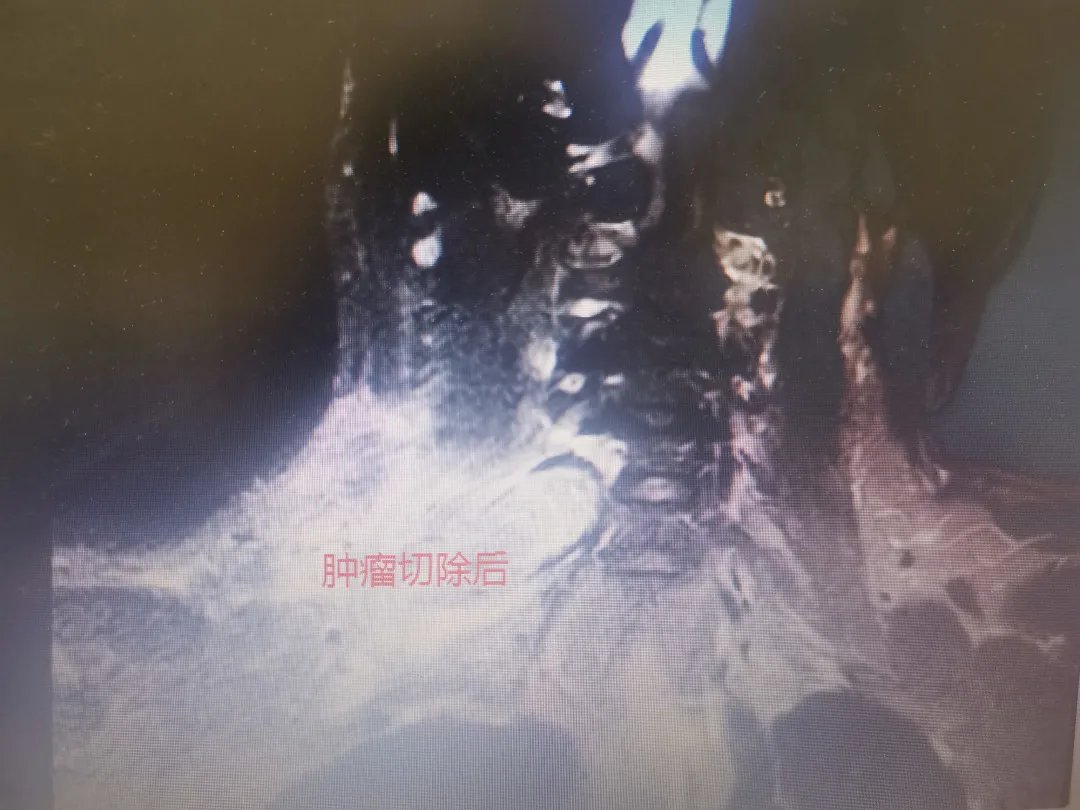

文章插图

术后头颈部MRI显示:肿瘤切除干净